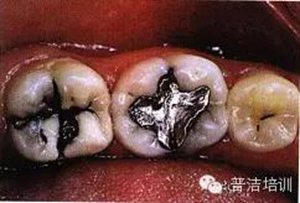

一、下頜后牙牙合面廣泛齲壞,檢查后決定行樹脂嵌體修復(fù)

二、去除齲壞的組織,可以使用送風(fēng)公司生產(chǎn)的齲齒檢測(cè)液來判斷齲壞的組織是否去除干凈